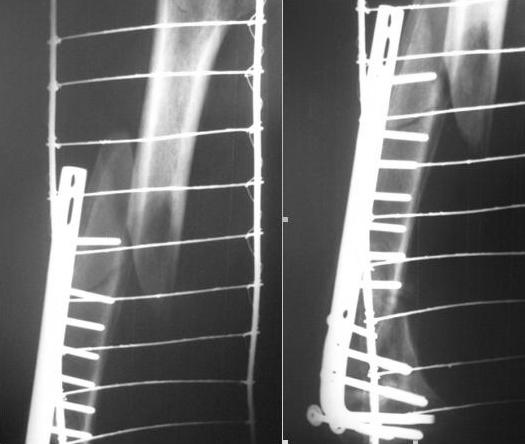

Уважаемые коллеги, хотелось бы услышать Ваше мнение по поводу выбора тактики лечения. Сегодня на дежурстве поступил пациент с переломом верхней\3 бедренной кости.

Из анамнеза в марте 2008 года оперирован по поводу внутрисуставного перелома дистального метаэпифиза бедренной кости. Выполнено МОС. На представленных рентгенограммах видно, что это стресс перелом с формирующимся ложным суставом дистального метафиза. Ваше мнение по поводу выбора тактики леченияСпасибо за ответ.

Уважаемый Владимир! К сожалению, по снимкам не видно, что именно там творится с дистальным метаэпифизом, а вообще напрашивается удаление всего этого металла и ретроградный интрамедуллярный блокируемый остеосинтез; в общем-то, наверное, с самого начала следовало применять именно его. Успехов!

Вообще, надо удалять пластину. Мы бы синтезировали гвоздем антеградно.

Все-таки хотелось бы увидеть более приличные рентгенограммы, т.е. фас и профиль на протяжении, с захватом суставов. По этим снимкам не спланировать действия на дистальном отделе бедра.

Снимки действительно оставляют желать лучшего. Но обязательно нужно смотреть первичные. у меня вообще сложилось мнение, что изначально не совсем удачно выбран метод о-за. Блокируемые гвозди в данной ситуации скорее самый лучший выход.